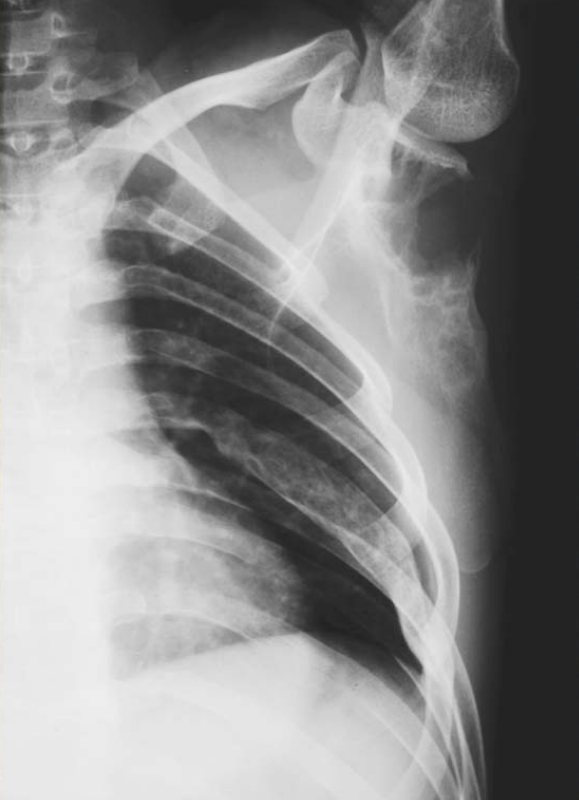

Figure3